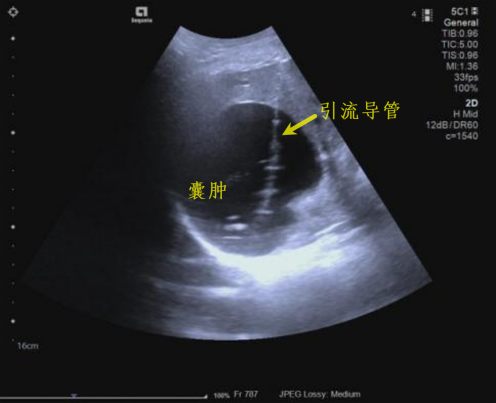

肝囊肿硬化治疗

囊肿硬化治疗 囊肿治疗后